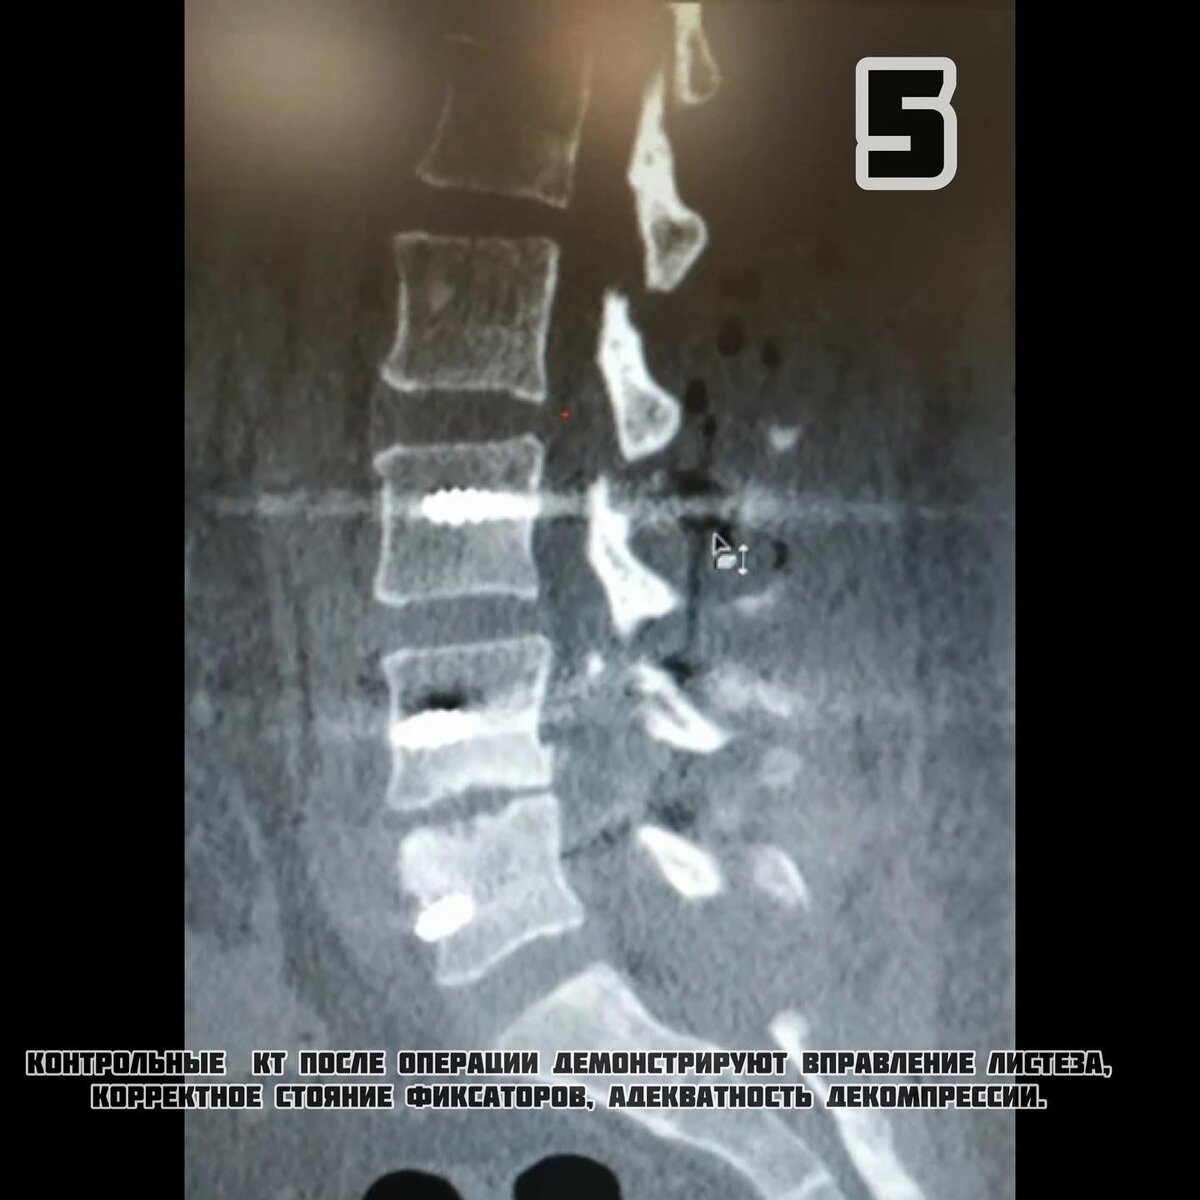

-5